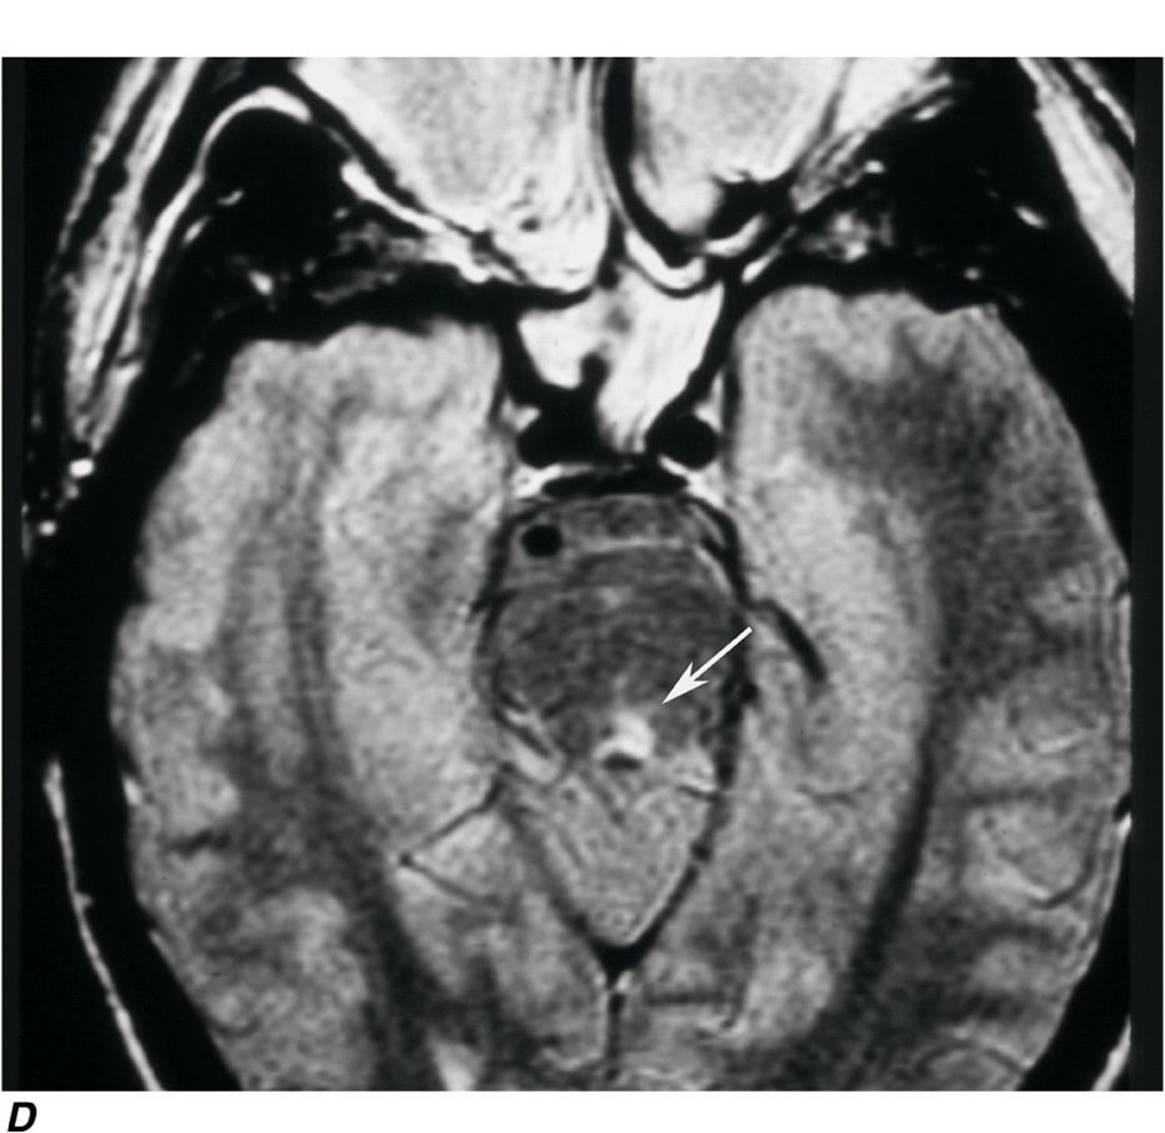

For some patients, optic neuritis remains an isolated event. However, the ONTT showed that the 15-year cumulative probability of developing clinically definite multiple sclerosis after optic neuritis is 50%. In patients with two or more demyelinating plaques on brain magnetic resonance (MR) imaging, treatment with interferon β-1a can retard the development of more lesions. In summary, an MR scan is recommended in every patient with a first attack of optic neuritis. When visual loss is severe (worse than 20/100), treatment with IV followed by oral glucocorticoids hastens recovery. If multiple lesions are present on the MR scan, treatment with interferon β-1a should be considered.